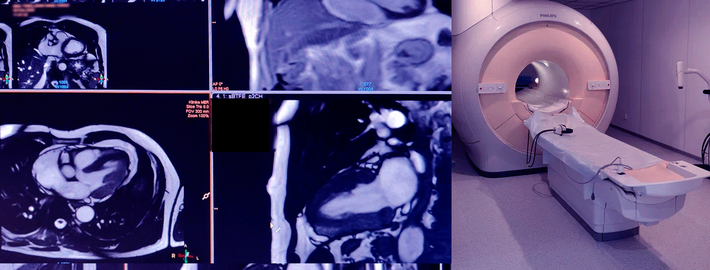

МРТ: сверхточная диагностика заболеваний сердца в Поликлинике на Скатертном

МРТ сердца проводит Аносов Андрей Александрович - врач-рентгенолог, стаж 19 лет. Имеет многолетний опыт высокоточной диагностики МРТ сердца. Проводит оценку структуры, правильности работы сердца, характеристик ткани, перфузии и наличий рубцов или фиброза.

Современное оборудование позволит сделать качественные, четкие снимки, которые станут залогом своевременной постановки диагноза;

МРТ позволит полноценно оценить структуру и функцию сердца, превосходя по точности оценки все инструментальные исследования.